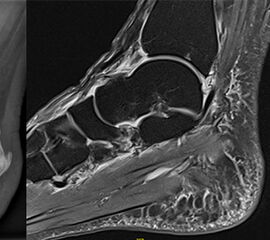

Offene Reposition und interne Fixierung (ORIF)

Die Versorgung der Processus anterior calcanei Frakturen erfolgt in der Regel über einen anterolateralen Zugang (alternativ Ollier-Zugang). Unter Schonung der Peronealsehnen sowie des N. cutaneus dorsalis intermedius erfolgt die Darstellung des Lig. bifurcatum. Die Fraktur sowie Gelenkflächen des CC-Gelenks werden sorgfältig inspiziert. Anschließend erfolgt die Reposition des Fragments/der Fragmente. Hierbei kann das Einbringen eines Kirschner-Drahts als „Joystick“ für die anatomische Reposition, insbesondere der CC-Gelenksfläche, hilfreich sein. Die Versorgung erfolgt mittels (Mini-/Kleinfragment-)Zugschrauben-Osteosynthese 11. Wie oben bereits aufgeführt bestehen nicht selten begleitende Bandverletzungen. Daher sollte im Anschluss an die osteosynthetische Versorgung stets eine Prüfung der Bandstabilität unter dem Bildwandler erfolgen. Bei entsprechender Instabilität wird eine temporäre Transfixation mittels Kirschner-Drähten empfohlen 11.

Zum Lesen der Bildbeschreibung und zur Vollansicht bitte das Bild anklicken. Bild: M. Walther

Die Ergebnisse der offenen Reposition und internen Fixierung bzw. Osteosynthese (ORIF) von Frakturen des PAC wird in vier Publikationen mit insgesamt 8 Patienten beschrieben 374011, (Pillai 2005). Zwei Arbeiten führten keine Klassifikation auf 3740, die beiden anderen führten die Operation bei Frakturen des Typs III nach Degan durch 11, (Pillai 2005). Nur drei Studien machen Angaben zum Frakturalter 4011, (Pillai 2005). Ein Fallbericht macht weder Angaben zum Frakturtyp noch zum Alter der Fraktur 37. Alle Autoren berichten über zufriedenstellende bis exzellente subjektive Behandlungsergebnisse 4011, (Pillai 2005), 37. Nur Ochman et al. erhoben zusätzlich einen objektivierbaren Zielparameter. Nach ORIF von fünf dislozierten Degan III Frakturen betrug der durchschnittliche AOFAS-Score 91 Punkte 11.

Bei entsprechendem Unfallmechanismus sollte differentialdiagnostisch immer an eine Fraktur des Processus anterior calcanei gedacht werden. Die Diagnosestellung kann heute mittels der hohen Verfügbarkeit schnittbildgebender Verfahren sicher und frühzeitig gelingen. Patienten mit akuter Fraktur und großem, disloziertem Fraktur-Fragment (Typ Degan III) können von der Durchführung einer Osteosynthese profitieren (Abb. 4). Aufgrund der guten Erfahrungen mit der früh-funktionellen Therapie mittels beschwerdeabhängiger Vollbelastung empfehlen die Autoren den Patienten die Operation im Rahmen der akuten Verletzung vor allem dann, wenn eine Instabilität im Chopart-Gelenk vorliegt. Zur Entscheidung werden Röntgenaufnahmen im seitlichen Strahlengang des Fußes unter Belastung angefertigt und auf eine Instabilität in der Chopart-Gelenklinie geachtet. Zusätzlich werden bei Verdacht auf eine Instabilität Stress-Aufnahmen des CC-Gelenkes durchgeführt. Fast alle Autoren führen eine Exzision der Fragmente nur dann durch, wenn sich die Beschwerden nicht bessern und es zur Ausbildung einer Pseudarthrose kommt.